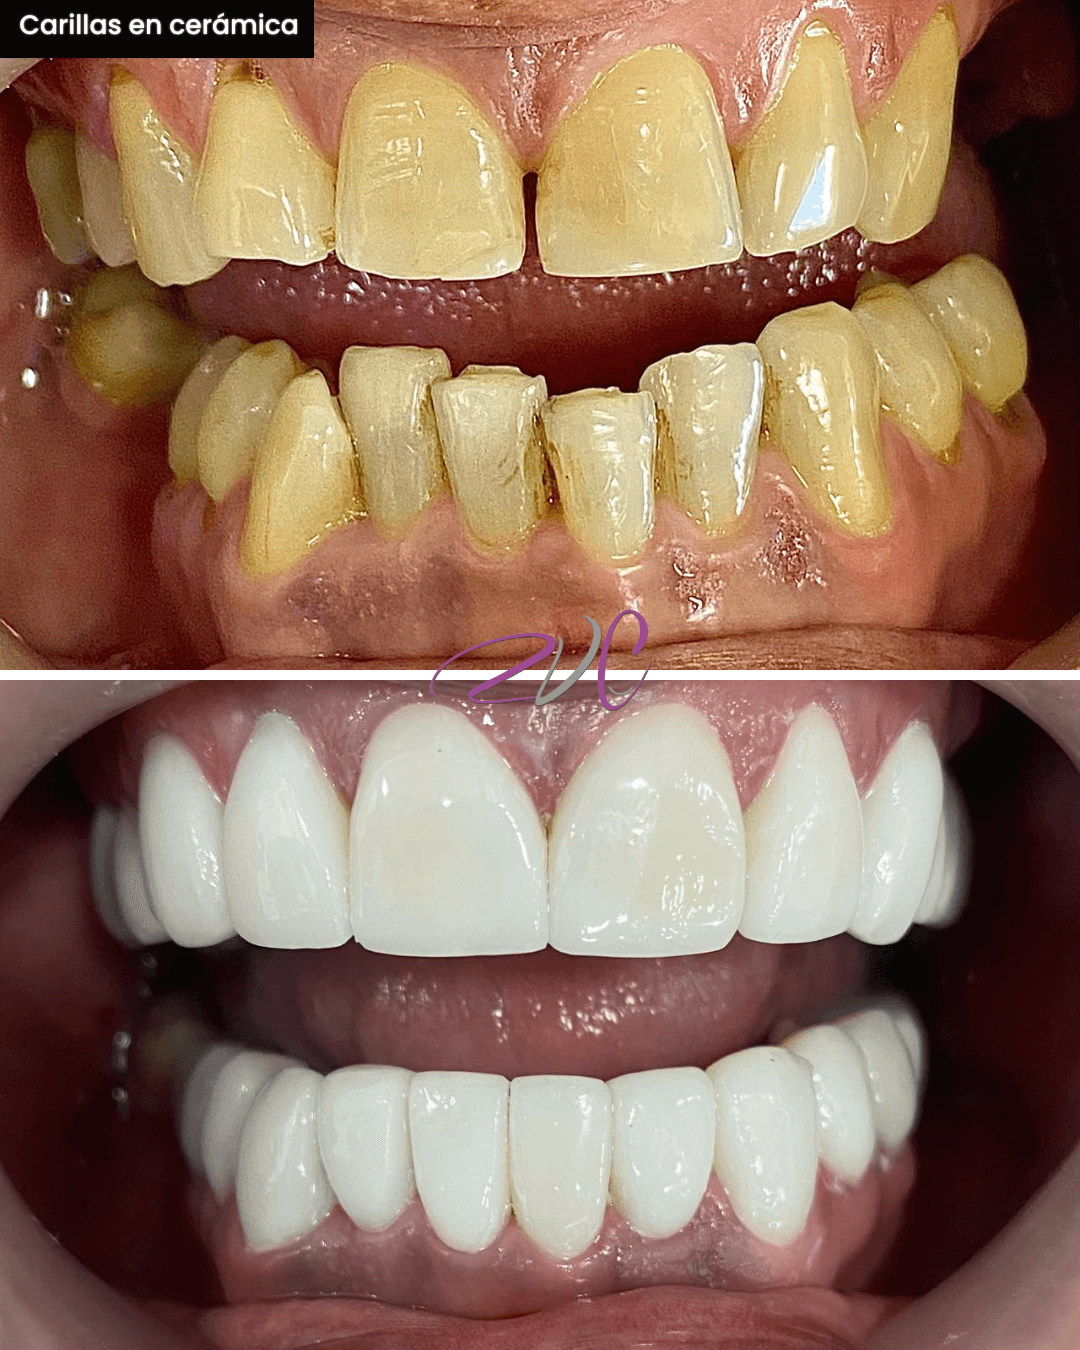

Odontología Estética

Conjunto de procedimientos que armonizan la sonrisa, mejorando su forma, color y alineación. Incluye diseño de sonrisa en resina o lente cerámico, microdiseño dental, contorneado estético y otros tratamientos personalizados según tu tipo de sonrisa.